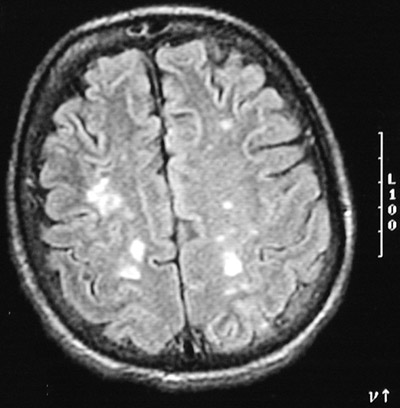

| The axial T2 weighted MRI scan above and the axial FLAIR MRI scan below, both of the cerebrum, reveal multiple bright embolic infarcts in a patient with infective endocarditis of mitral and aortic valves. Since the emboli may not completely occlude the vessel, there can be hemorrhage into the infarct. |